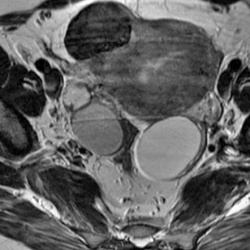

Попалось интересное наблюдение.Обнаружены эндометриома, фиброма и киста. Интересно, что где?